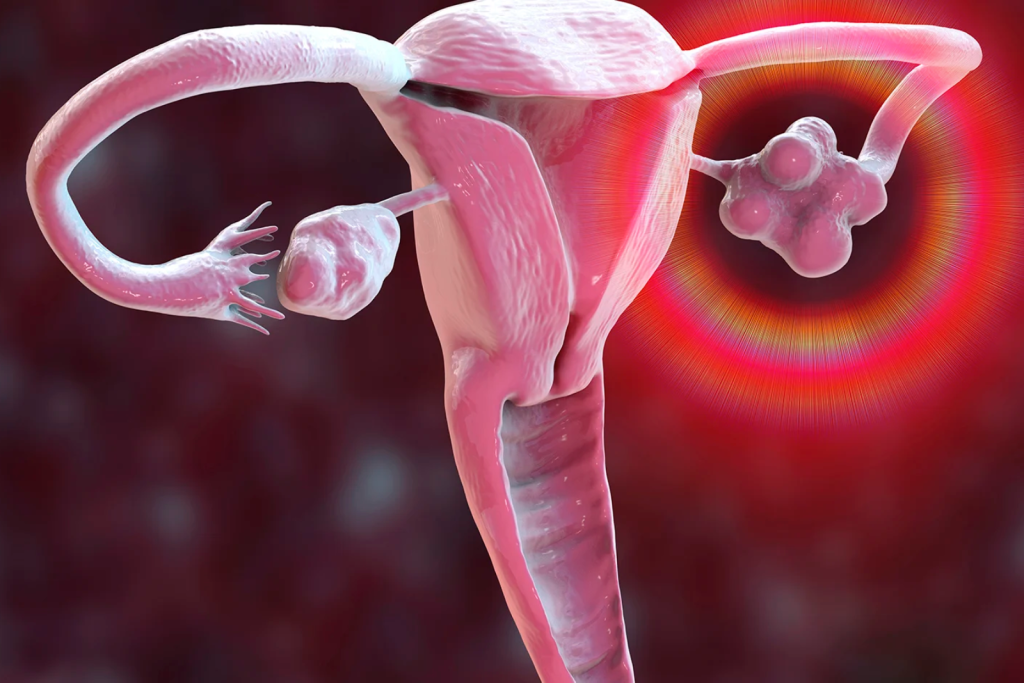

Polycystic Ovarian Syndrome

Hypogonadism